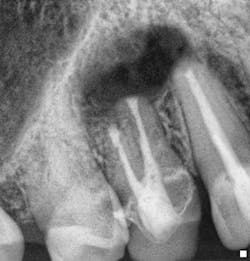

Fig. 6: Surgical preop radiograph. Endodontic treatment was necessary due to the presence of periapical pathology and acute symptoms, despite the radiographic appearance of the existing endodontic treatment being technically satisfactory. The presence of a long post, which is possibly serrated in nature and potentially actively engaging the root structure, is likely to compromise the potential for post removal and increase the risk of root fracture initiation, which would jeopardize the long-term survival of the tooth.

Fig. 7: Surgical postop radiograph. Surgical endodontic treatment was performed and the apical 3 mm to 4 mm of the root was reprepared using ultrasonics and sealed with MTA. A bone graft and resorbable membrane were placed to maximize the potential for osseous and soft tissue healing, especially with the proximity of the maxillary sinus to the surgical site.Case 2